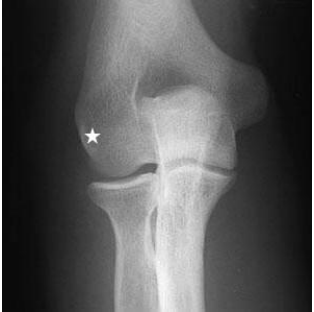

32 附圖為手肘前後位成像(AP view)的 X 光片,其中以白色星狀標示的結構為何?

(A)肱骨外上髁 (B)肱骨內上髁 (C)橈骨頭 (D)肱骨鷹嘴窩